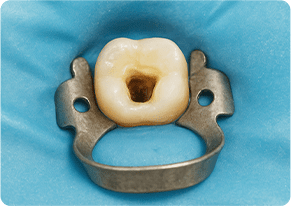

主訴 奥歯で噛むと痛い

治療期間/回数 1ヵ月、3回

価格(税込) 88,000円

リスク・副作用 病変再発、歯根破折の可能性

ポイント う蝕検知液を用い、むし歯の取り残しが無いようにし、ラバーダム防湿を行い、無菌的に根管治療を行った。根管充填材は、殺菌作用の強い保険適応外のMTAセメントを使用した。